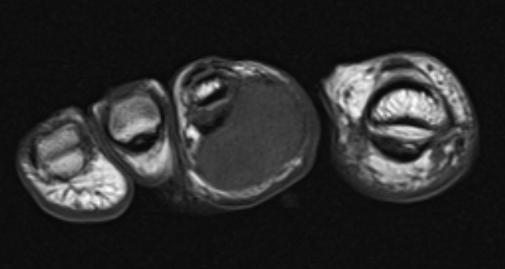

GCT of tibialis posterior tendon sheath

- heterogenous mass on MRI

- biopsy - abundant giant cells